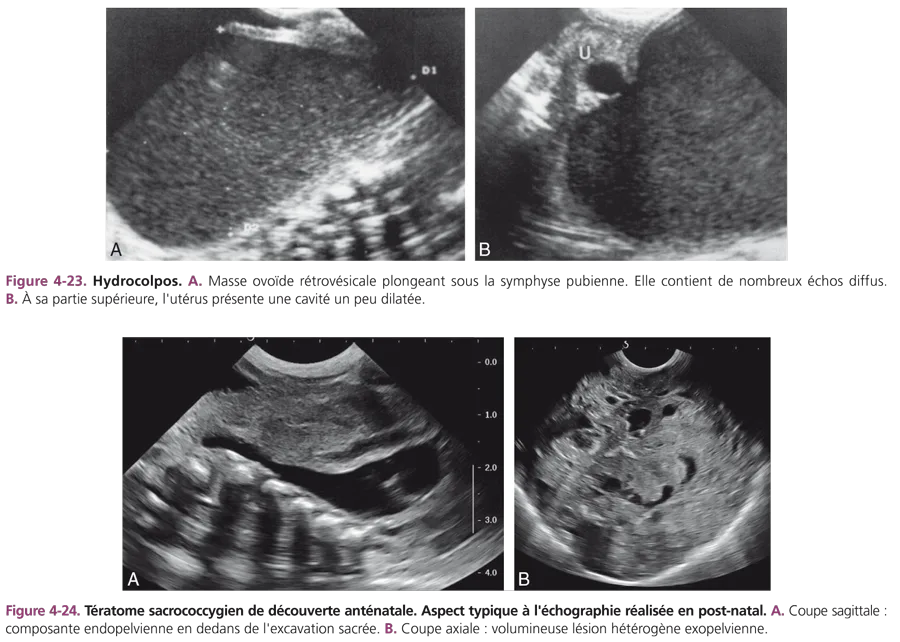

Hydrocolpos ou hydrométrocolpos

Il est secondaire à une malformation vaginale plus ou moins complexe. Il est souvent découvert à la naissance dans un tableau clinique de polymalformations : imperforation anale, malformation urogénitale, cardiopathie, polydactylie. Cliniquement et échographiquement, l’hydrocolpos diffère du kyste de l’ovaire car il est médian, fixe et plonge sous la symphyse pubienne (fig. 4-23). La rétention est rarement liquidienne pure, elle contient souvent des mucosités formant un sédiment déclive ou homogène. La cavité utérine sus-jacente peut être dilatée ou non. Dans le cadre d’une duplicité, la malformation associe classiquement un hémihydrocolpos et une agénésie rénale unilatérale.

Tératome sacrococcygien

Peu fréquente, cette tumeur touche quatre fois plus souvent les filles que les garçons. Son diagnostic est actuellement anténatal. À la naissance, il s’agit d’une masse sacrococcygienne, extériorisée à la fesse et/ou au périnée. Dix pour cent de ces tumeurs ont un développement purement endopelvien, présacré, rétrorectal. Bien que 95 % des tératomes sacrococcygiens soient bénins, le dosage de l’alpha-foetoprotéine et des gonadotrophines sériques doit être pratiqué, avant toute intervention chirurgicale d’exérèse. Le cliché d’ASP est caractéristique lorsqu’il montre des malformations vertébrales sacrées et des calcifications intratumorales. L’échostructure de la masse intra- et extrapelvienne est hétérogène, contenant des éléments liquidiens et solides (fig. 4-24). L’examen tomodensitométrique montre les contingents graisseux et les petites calcifications. L’IRM précise l’extension périnéale et intrarachidienne par les trous sacrés.